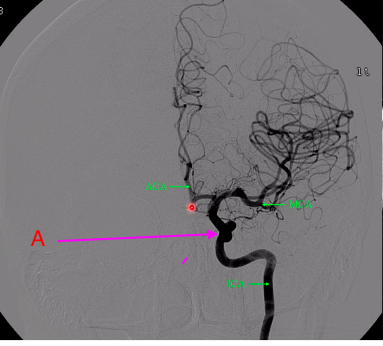

what is A?

cavernous sinus